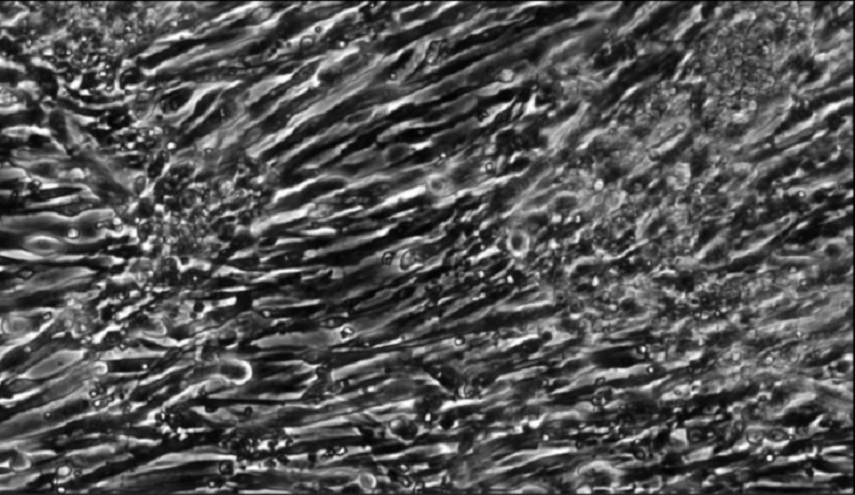

علوم وتكنواوجيا _الكوثر: تمكن العلماء من إنماء عضلات فعالة باستخدام الخلايا الجذعية التي تم إنشاؤها من الجلد.

ويحمل هذا الاختراق العلمي وعدا لفهم وعلاج أمراض العضلات النادرة. وتم زراعة العضلات باستخدام خلايا الجلد التي أُعيدت برمجتها إلى الحالة الأصلية، ويُشار إليها باسم الخلايا الجذعية المحفزة.

ويمكن بعد ذلك تشجيع هذه الخلايا على النمو في خلايا العضلات، عن طريق "إغراقها" بمادة تسمى Pax7.

وقدم العلماء لخلايا العضلات المنتجة بهذه الطريقة، الدعم الهيكلي والتغذية التي سمحت لها بأن تصبح عضلات فعالة.

ولم تستجب العضلات للإشارات الكيميائية والكهربائية فقط، مثل العضلات الحية، بل كان العلماء قادرين على زراعتها في الفئران بنجاح نسبي.

وعلى الرغم من أن العضلات لم تكن قوية مثل الأنسجة العضلية التقليدية، إلا أنها عملت داخل الفئران وبدأت بالاندماج في العضلات الموجودة مسبقا.